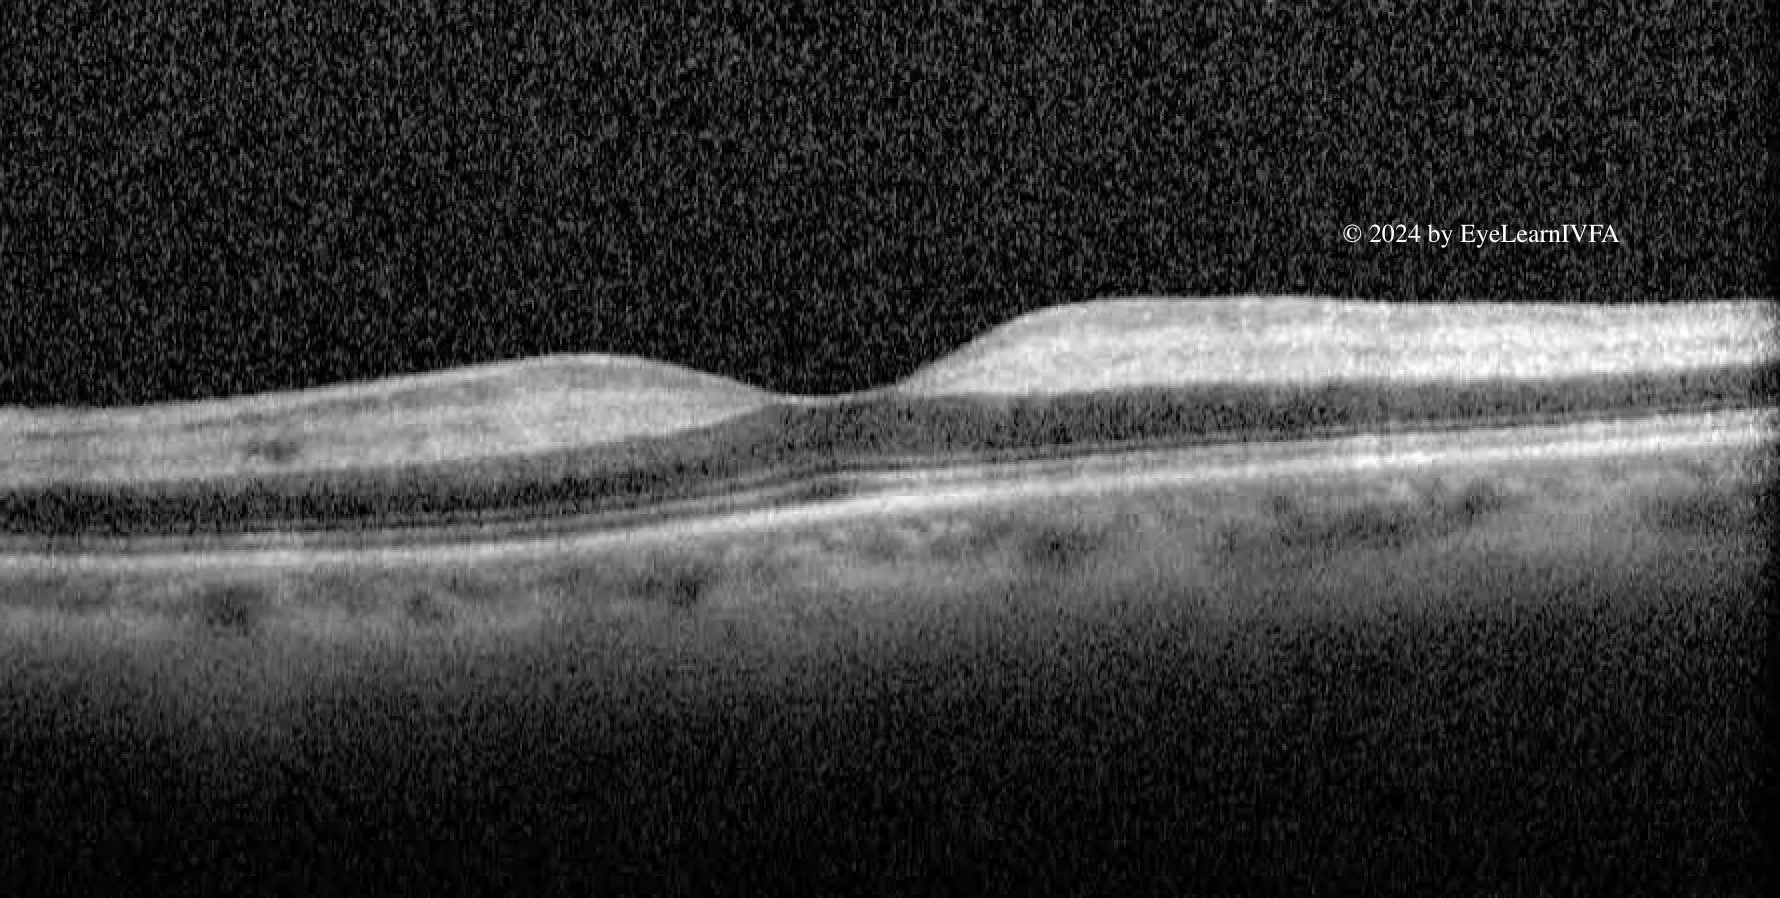

• The diagnosis is arteritic anterior ischemic optic neuropathy (AAION) secondary to giant cell arteritis (GCA). IVFA shows delayed choroidal filling with prolonged arteriovenous filling - a hallmark of posterior ciliary artery ischemia in GCA. These findings, combined with sudden vision loss, proceeding jaw pain, elevated inflammatory serological markers, a hyper-reflective OCT and subtle cherry red spot on clinical examination all point towards AAION related to giant cell arteritis.